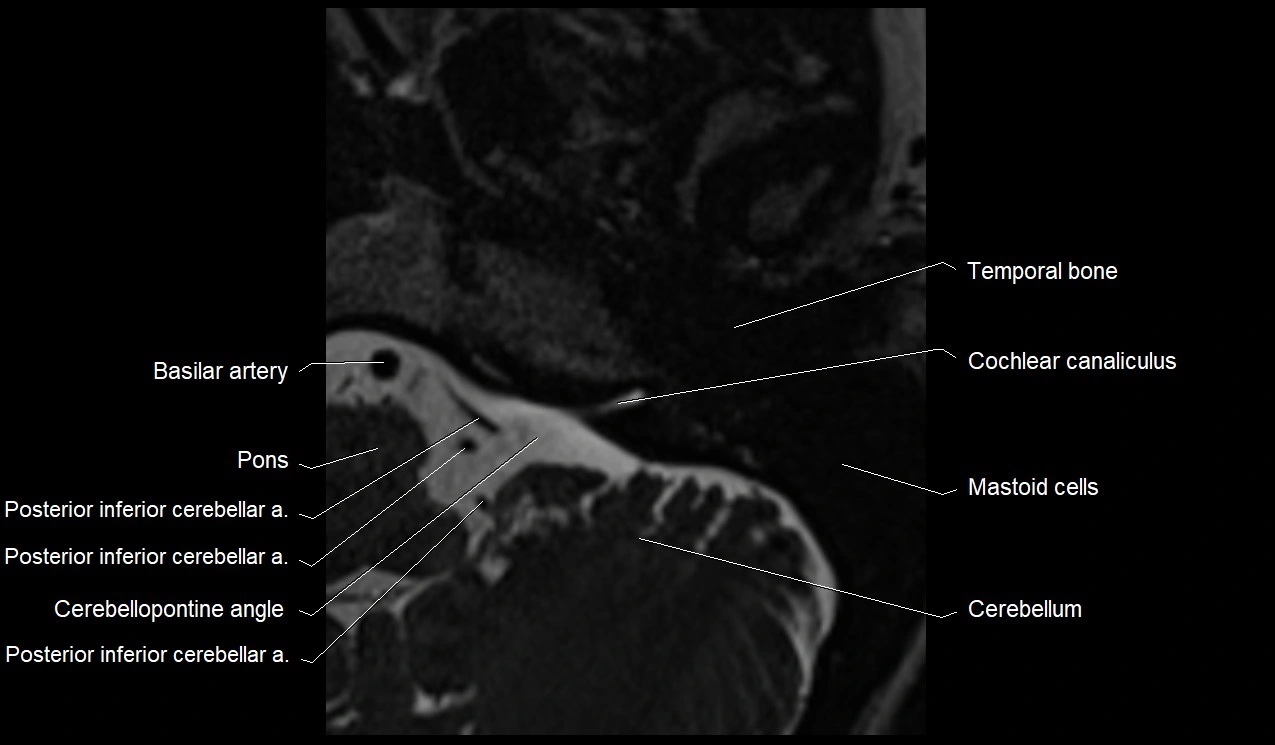

image